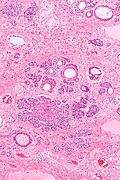

| LM | typically well-circumscribed cell nest in the superficial dermis, surrounding by a fibrous stroma, basaloid cells - usu. with peripheral palisading +/-surround keratin-filled cysts, fibroblasts-like cell aggregate, similar to a follicular papillae (papillary-mesenchymal body) |

Features:[3]

- Well-circumscribed cell nest in the superficial dermis.

- Surrounding by a fibrous stroma.

- Basaloid cells with peripheral palisading.

- +/-Surround keratin-filled cysts.

- Fibroblasts-like cell aggregate, similar to a follicular papillae (papillary-mesenchymal body).

Trichoepithelioma - low mag. (WC/Nephron)

- Trichoepithelioma - intermed mag.jpg

Trichoepithelioma - intermed. mag. (WC/Nephron)